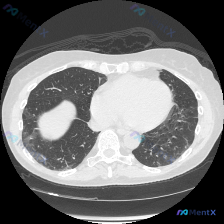

看到这个胸部CT的影像资料,整理了完整读片和分析思路,分享给大家讨论 一、影像基本情况 这是胸部CT肺窗横断面影像,解剖结构观察结果如下: 1. 肺实质:双肺存在非对称性分布的异常密度影,右肺(图像左侧)可见大范围磨玻璃密度影(GGO),主要分布在肺外周及胸膜下,边界模糊,部分区域密度稍高;左肺(图...